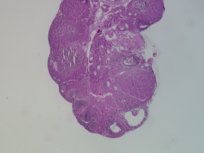

Genus: Mus (mice)

Species: Mus musculus ()

Donor ID: SX_MM_Treatment_5

Life Stage: prepubertal

Age: 0 years, 25 days

Accession #: MDB0000573

Ovary position: unspecified

Location: wholeOvary

Section thickness: 5 microns

Fixation: neutralBufferedFormalin10

Stain: Hematoxylin and Eosin

Immunohistochemistry: None

Experimental treatment: Yes - PFNA, 25 mg/kg, IP injection, 5 days

Other pathology: None